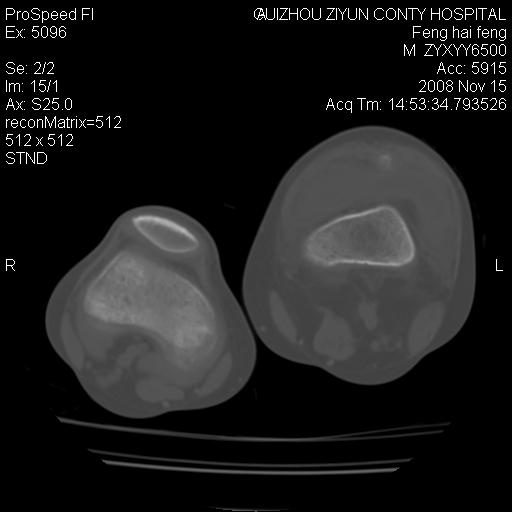

标题: CT16656:M 14Y 左膝关节肿胀一年余。其余病史不详。 [打印本页]

标题: CT16656:M 14Y 左膝关节肿胀一年余。其余病史不详。

考虑左侧髌骨结核;左膝关节滑膜肿胀、增厚,关节囊积液。

左膝滑膜型关节结核可能性大!支持!滑膜型关节结核主要ct表现:关节囊肿胀,积液,关节面见小破坏灶,并见点状死骨!

好大的左腿!考虑左侧髌骨结核,左膝关节滑膜肿胀、增厚,关节囊积液。

左侧髌骨结核;左膝关节滑膜肿胀、增厚,关节囊积液